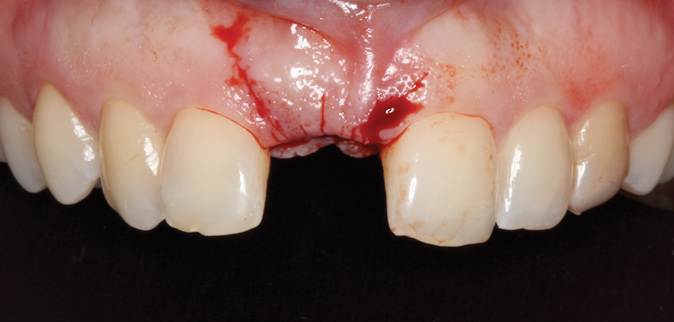

A 33-year-old woman presented with a buccal fistula at the apex of No. 8, and there was an 8-mm mid-buccal probing depth (Figure 1). The tooth had been treated multiple times by an endodontist. Based on the tooth's dental history, mobility, and its poor endodontic and periodontal prognosis, it was deemed hopeless and scheduled for extraction (Figure 2).

Fig 1. Fistulous tract at apex of tooth No. 8 (arrow).

Figure 1